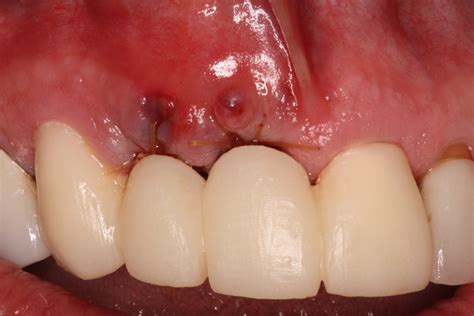

The process of placing a bone graft after tooth extraction is typically performed during the same appointment as the extraction itself. Once the tooth is removed, the dentist cleans the socket thoroughly to ensure no infection remains. The grafting material is then carefully packed into the space. A membrane is often placed over the site to hold the graft in place and protect the area from soft tissue ingrowth, ensuring the bone has the best chance to mature.

A bone graft after tooth extraction, often referred to as "socket preservation," serves as a scaffold for your body to grow new, healthy bone. By filling the empty socket with grafting material, your dentist creates a environment that encourages your natural bone cells to regenerate and integrate with the graft, effectively stopping the bone loss process before it starts.